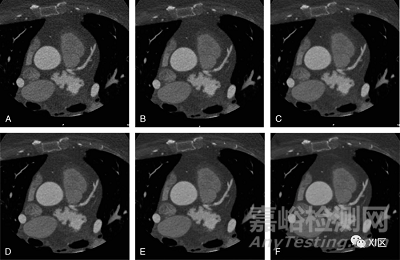

最近,基于神經(jīng)網(wǎng)絡(luò)的深度學(xué)習(xí)的圖像重建(DLIR)算法正在出現(xiàn):GE Healthcare的TrueFidelity(TF)和Canon Medical Systems的Advanced Intelligent Clear-IQ Engine(AiCE)。圖2、3和4顯示了用FBP、ASIR-V、TF和iDose4在不同水平上重建的CT掃描的例子。

圖3 用不同水平的ASiR-V和DLIR算法重建的CT圖像的比較。一名82歲女性的軸位冠狀動脈CT血管造影術(shù)掃描在100 kVp和200 mAs的固定管電流下進(jìn)行。用ASiR-V 30%(A)、50%(B)和80%(C)的不同強(qiáng)度以及低(D)、中(E)和高(F)水平的DLIR重建掃描。中等強(qiáng)度水平(通常為50%至80%)的迭代重建顯示圖像噪聲和圖像質(zhì)量之間的平衡得到了改善:特別是,IR顯示血管細(xì)節(jié)的可視化更好,斑塊輪廓的模糊程度更低。